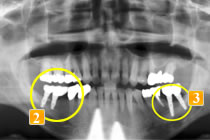

61歳男性

初診時、歯の根の先にかなり大きな膿の袋ができてしまっています(

)。

根が割れている、ひびが入っているという可能性も大いにありました。

は本来なら抜歯するケースですが、何とか残せないかと一度抜いて根の治療をし、再度植えました(

)。“再植術”といいます。

は最初の状態と同じ様にブリッジにすると負担が大きく、すぐダメになってしまう可能性が高いと判断し、同様に、この歯を何とか残すために歯のない部分はインプラントという治療法を選択しました。これならつながないでいいですし、インプラントでも噛む力が負担できるのでほかの歯を守れます。

歯がない部位(

)にはインプラントを植立しました。もし再度ブリッジにした場合

再植した歯への負担過重によって痛みが出れば、支えているもう一方の歯への負担も増します。

そうして負担が増加することで、右下奥歯は2本欠損することになったかもしれないのです。 しかし、この3本の歯をそれぞれ独立させることで、相互に保護しあう状態となり、結果、歯を残すことができました。